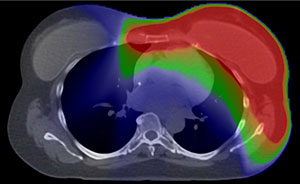

Conventional X-Ray Therapy

Red: High Radiation Dose |

Green: Intermediate Radiation Dose |

Blue: Low Radiation Dose